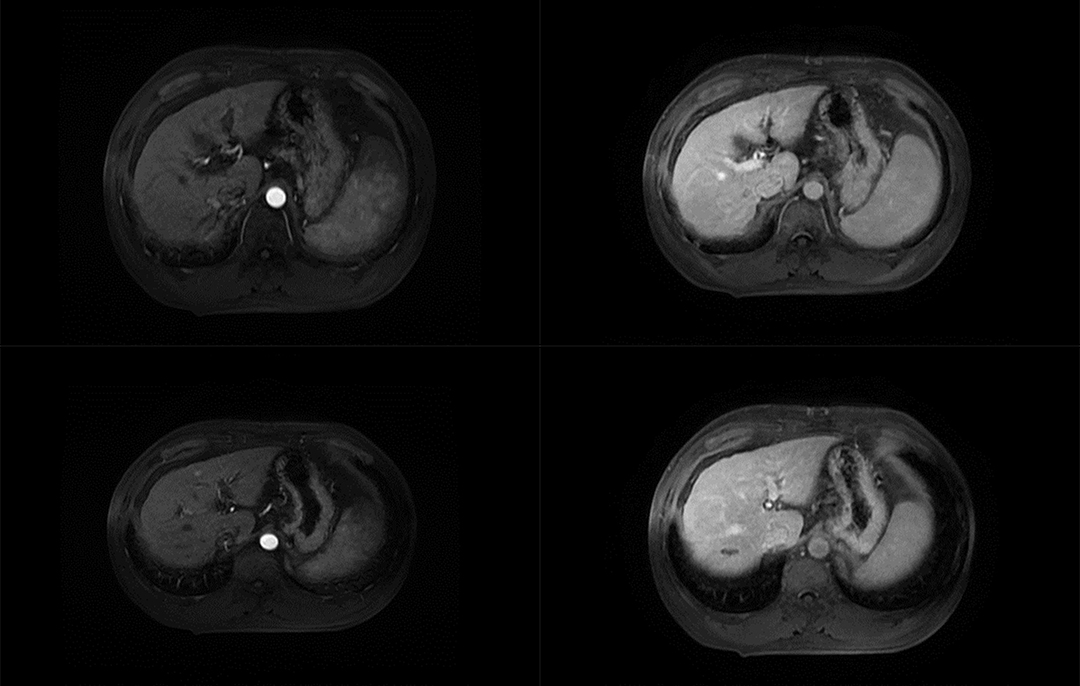

▲ 患者一术前影像

44岁男性,因“诊断HCC2年余,腹痛1周。”入院,完善上腹部MRI及肿瘤指标,考虑肿瘤复发.影像检查显示:肝S3段异常信号范围较前略增大。综合平扫+DWI诊断:肝S3、4、8段异常信号,考虑Ca介入术后改变,未见明显活性残留,肝S3段考虑Ca复发,范围较前略增大。肝尾叶略大,肝实质多发增生结节。病灶大小约为3.5(左右)x3cm(胸背)x3cm(头足)。

▲ 患者二术前影像

前影像